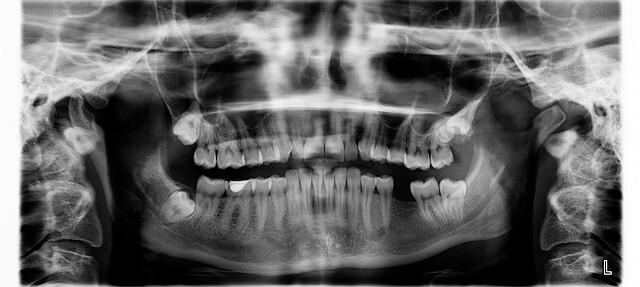

* 65세이상 노인 의료 혜택 중 또 하나 주목할 부분은 치과 치료 지원입니다. 건강보험이 적용돼 틀니, 임플란트 본인 부담금이 30%로 줄었습니다. 최대 4개까지 지원 가능하며, 의료급여 수급자는 10% 부담입니다. 가까운 치과 방문 시 검진과 함께 신청할 수 있어 편리합니다.

65세이상 노인 의료 혜택에 대해 제가 직접 경험한 내용을 바탕으로 말씀드리겠습니다. 저희 부모님이 만 65세를 넘어서면서 적용받은 가장 큰 혜택은 틀니 및 임플란트 비용 지원입니다. 건강보험 적용으로 실제 비용 부담이 크게 줄었고, 최대 2개의 임플란트에 대해 70%가 지원되니 경제적 부담이 상당히 덜해졌습니다. 이외에도 골다공증 검사, 치매 조기검진 등 예방적 건강검진이 무료로 제공되어 건강관리 부담 완화에 큰 도움이 되죠.

제가 직접 경험한 바에 의하면, 65세이상 노인 치과의료 혜택은 건강보험에서 틀니부터 임플란트까지 폭넓게 지원합니다. 특히, 치아 상실로 고생하던 어르신들에게 좋은 소식입니다. 임플란트는 최대 2개까지 건강보험 혜택이 적용되어 본인 부담금이 30% 정도에 불과합니다.

| 틀니 및 임플란트 | 건강보험 적용, 최대 2개 임플란트 70% 지원 | 만 65세 이상 건강보험 가입자 | 본인 부담금 약 30% |

치과 임플란트 지원은 몇 개까지 가능한가요?

최대 2개까지 건강보험에서 70% 지원받을 수 있습니다.

- 의료비 지원: 치과 치료(틀니, 임플란트)의 본인 부담률을 30%로 낮추고, 건강보험이 적용되어 경제적 부담이 크게 줄어듭니다.

실제로 체감한 65세이상 노인 의료 혜택의 가치

제가 직접 경험한 65세이상 노인 의료 혜택 중 가장 큰 변화는 틀니 및 임플란트 지원 덕분에 가족들이 경제적 부담 없이 치과 치료를 받을 수 있었다는 점입니다. 본인부담률 30% 제도 적용으로 고액의 치과 치료비를 절감할 수 있었고, 품질 좋은 치료를 받으며 건강한 구강 상태를 유지할 수 있었습니다.